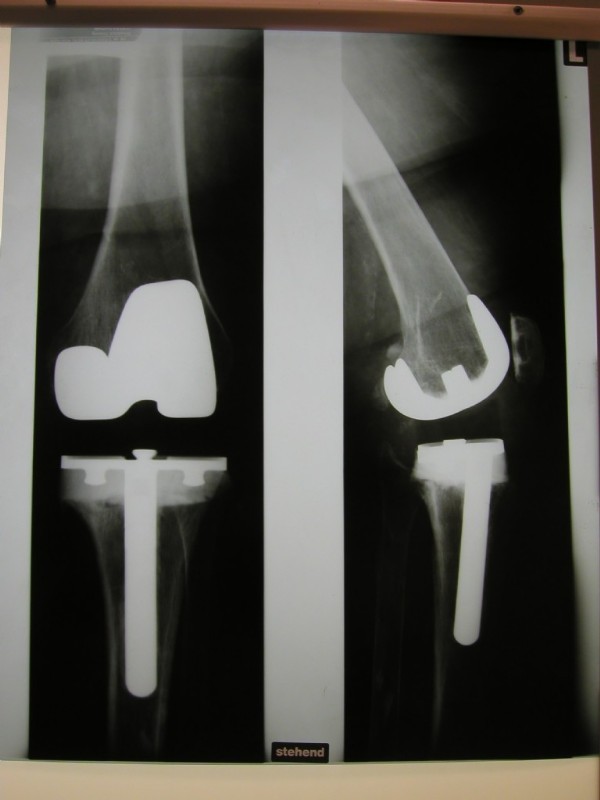

Partial prothesis. Only the iner part is replaced. We apply this procedure very rarely.

An older total endoprothesis inluding replacement of the kneecap. However, today, we replace kneecaps only very rarely.

Left: Here an existing, elsewhere placed prosthesis was changed because of loosening, and due to bone loss the height had to built up on the shin.

Center left and center right: A modern knee prosthesis with sparing bone removal and sliding surface replacement. Such knee joints are used routinely by us. They are made for the particular patients affected knee.